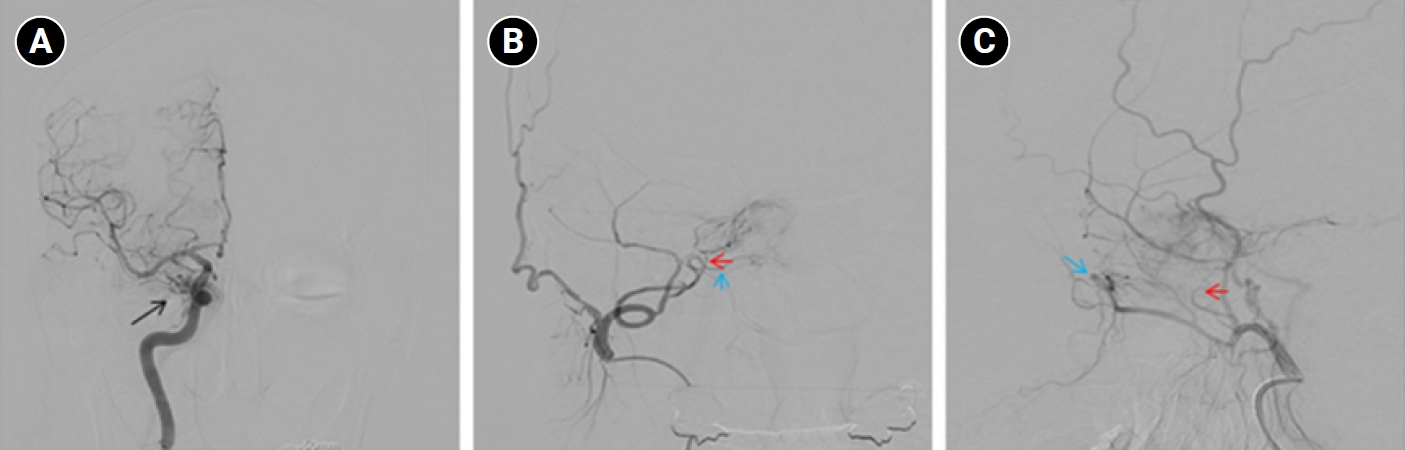

Baseline hematology and chemistry—including complete blood count, electrolytes, renal/hepatic indices—and coagulation tests (prothrombin time/international normalized ratio, activated partial thromboplastin time) were within reference limits. Erythrocyte sedimentation rate and C-reactive protein were normal. A focused screen for secondary trigeminal neuropathy (thyroid-stimulating hormone, vitamin B12, HbA1c) was negative. There were no clinical signs of infection. Brain magnetic resonance imaging (MRI) demonstrated high flow related signal in the right cavernous sinus and asymmetric dilation of the superior ophthalmic veins (right>left), raising suspicion for a CCF (Figure 1). Definitive diagnosis was established on digital subtraction angiography (DSA), which identified a right CCF. DSA demonstrated an indirect CCF supplied by the right meningohypophyseal trunk of the ICA and by right ECA branches, including the internal maxillary artery and the cavernous branch of the middle meningeal artery, consistent with Barrow type D (Figure 2).6 Barrow type D denotes an indirect, low-flow fistula with dual ICA/ECA dural supply; unlike direct type, indirect types present more insidiously, and symptom patterns are largely determined by venous drainage, with posterior drainage often manifesting as CN VI palsy and headache (Table 1).1,3,6,7 The fistula was treated with transvenous Onyx embolization. On post-procedure day 1, non-contrast time-of-flight magnetic resonance angiography (TOF-MRA) demonstrated a marked reduction of flow related hyperintensity within the right cavernous sinus, and the right superior ophthalmic vein caliber decreased from 6.63 to 4.61 mm (Figure 3A, B). Follow-up DSA (at 3 weeks) likewise showed substantial attenuation of fistulous opacification (Figure 3C), supporting a significant interval decrease in arteriovenous shunting. At 1–2 weeks, the patient reported an ~80%–90% reduction in dental/lower-facial pain and bifrontal headache from NRS 7–8 to 1–2. By 1 month, red-glass testing demonstrated resolution of primary-position diplopia. Formal prism measurements were unavailable; bedside ocular-motor grading was recorded using a standard duction underaction scale (–4 to 0). Right abduction improved from –1 to 0, and primary-position diplopia was absent at distance and near, consistent with recovery from abducens palsy.

Figure 3.Imaging changes before and after embolization. (A) Brain magnetic resonance imaging (coronal section through the orbits) shows a decrease in the diameter of the right superior ophthalmic vein from 6.63 mm pre-embolization to 4.61 mm post-embolization, indicating reduced venous congestion. (B) Axial time-of-flight magnetic resonance angiography demonstrates that flow-related hyperintensity within the right cavernous sinus is markedly reduced after embolization (red arrows), consistent with decreased shunt flow. (C) Digital subtraction angiography images before embolization show abnormal early pericavernous venous filling along the right cavernous sinus region (blue arrows), compatible with carotid-cavernous shunting. On follow-up, this abnormal filling is no longer visualized, consistent with interval reduction in shunt flow.